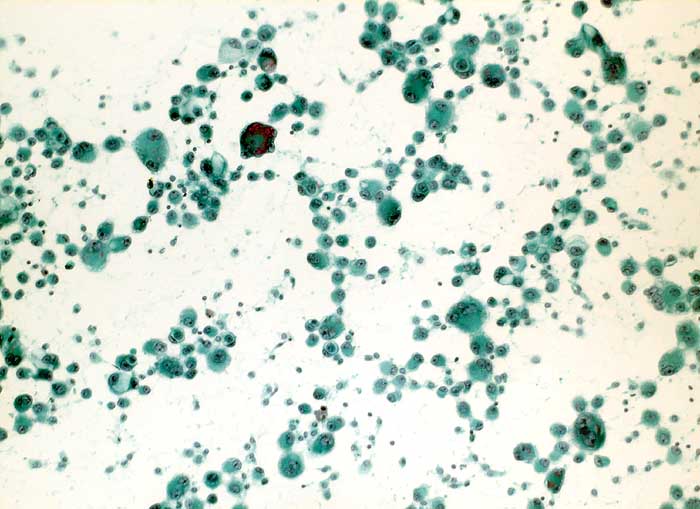

l/ Maligner Pleuraerguss: Adenokarzinom der Lunge

Maligner Pleuraerguss: Adenokarzinom der Lunge

Pleuraerguss Zytologie

Folgendes Antikörperpanel eignet sich für die Bestätigung der Verdachtsdiagnose einer Pleurakarzinose eines primären Bronchuskarzinoms: BerEP4 (Adenokarzinom positiv), TTF1 (Lungen- und Schilddrüsenkarzinom positiv), Calretinin (Mesothelien positiv) und Vimentin (Mesothelien positiv).